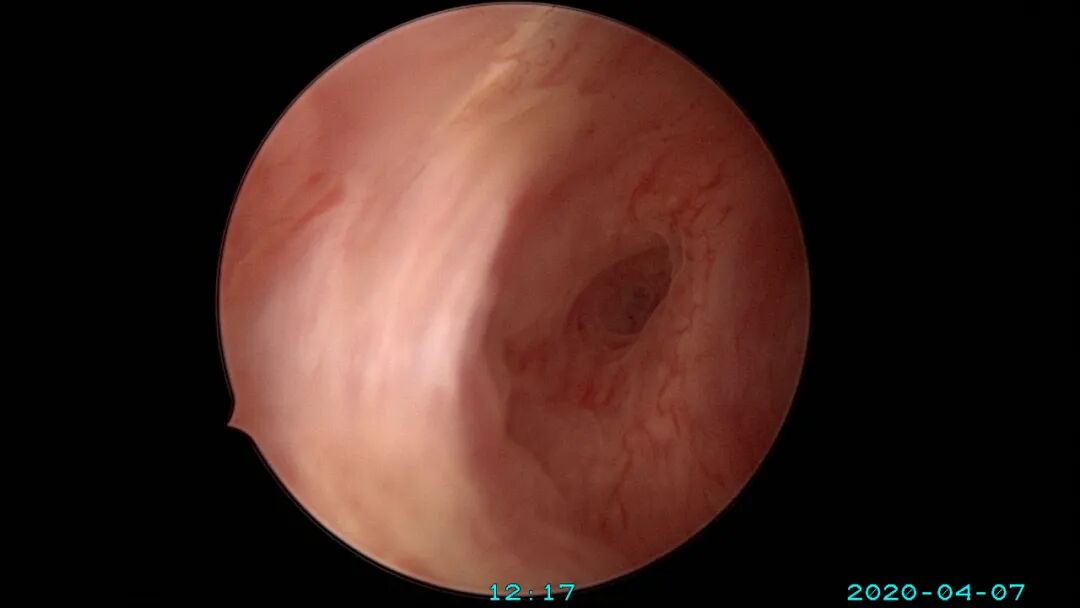

6、减少内膜损伤及输卵管开口周围损伤

个体化选择手术器械,减少内膜损伤及内膜丢失:冷刀优于能量器械,双极优于单级,电针优于电切环。能量器械设置最低有效能量,少用电凝。尽量避免探查宫深及扩宫操作,宫腔镜直视下进入宫腔,必要时采用阴道内镜方式进入,保持宫颈管及宫腔原始状态显露在宫腔镜下,不破坏病灶,便于准确诊断,精准手术。非要扩宫时,选择尖头扩宫棒,方便操作。宫颈外口狭窄或封闭时,可用尖刀片切开宫颈外口,必要时缝合牵拉宫颈再做切开,切口术后可不缝合。输卵管开口是精子和胚胎运行的重要关口,形态多样,开口周围颜色比内膜颜色浅(未被损伤的输卵管开口美兰不着色),粘膜平滑而薄,呈放射状。宫腔镜手术不要损伤输卵管开口,开口周围息肉、粘连等病变可以用微型剪、异物钳或电针处理,尽量不用电切环。宫腔镜微创理念牢记心中:手术要有助于生殖、有助于恢复月经、有助于减少粘连复发。术中保存完整手术资料,除了拍照,必要时开启摄像功能,录制手术视频,利于术后复盘手术过程,作为分析、学习、讨论、反思、提高等资料备用。

尽量保护输卵管开口周围内膜不受损伤,术中仅显露出左侧输卵管开口。该患者术后自然妊娠,34+周剖宫产分娩